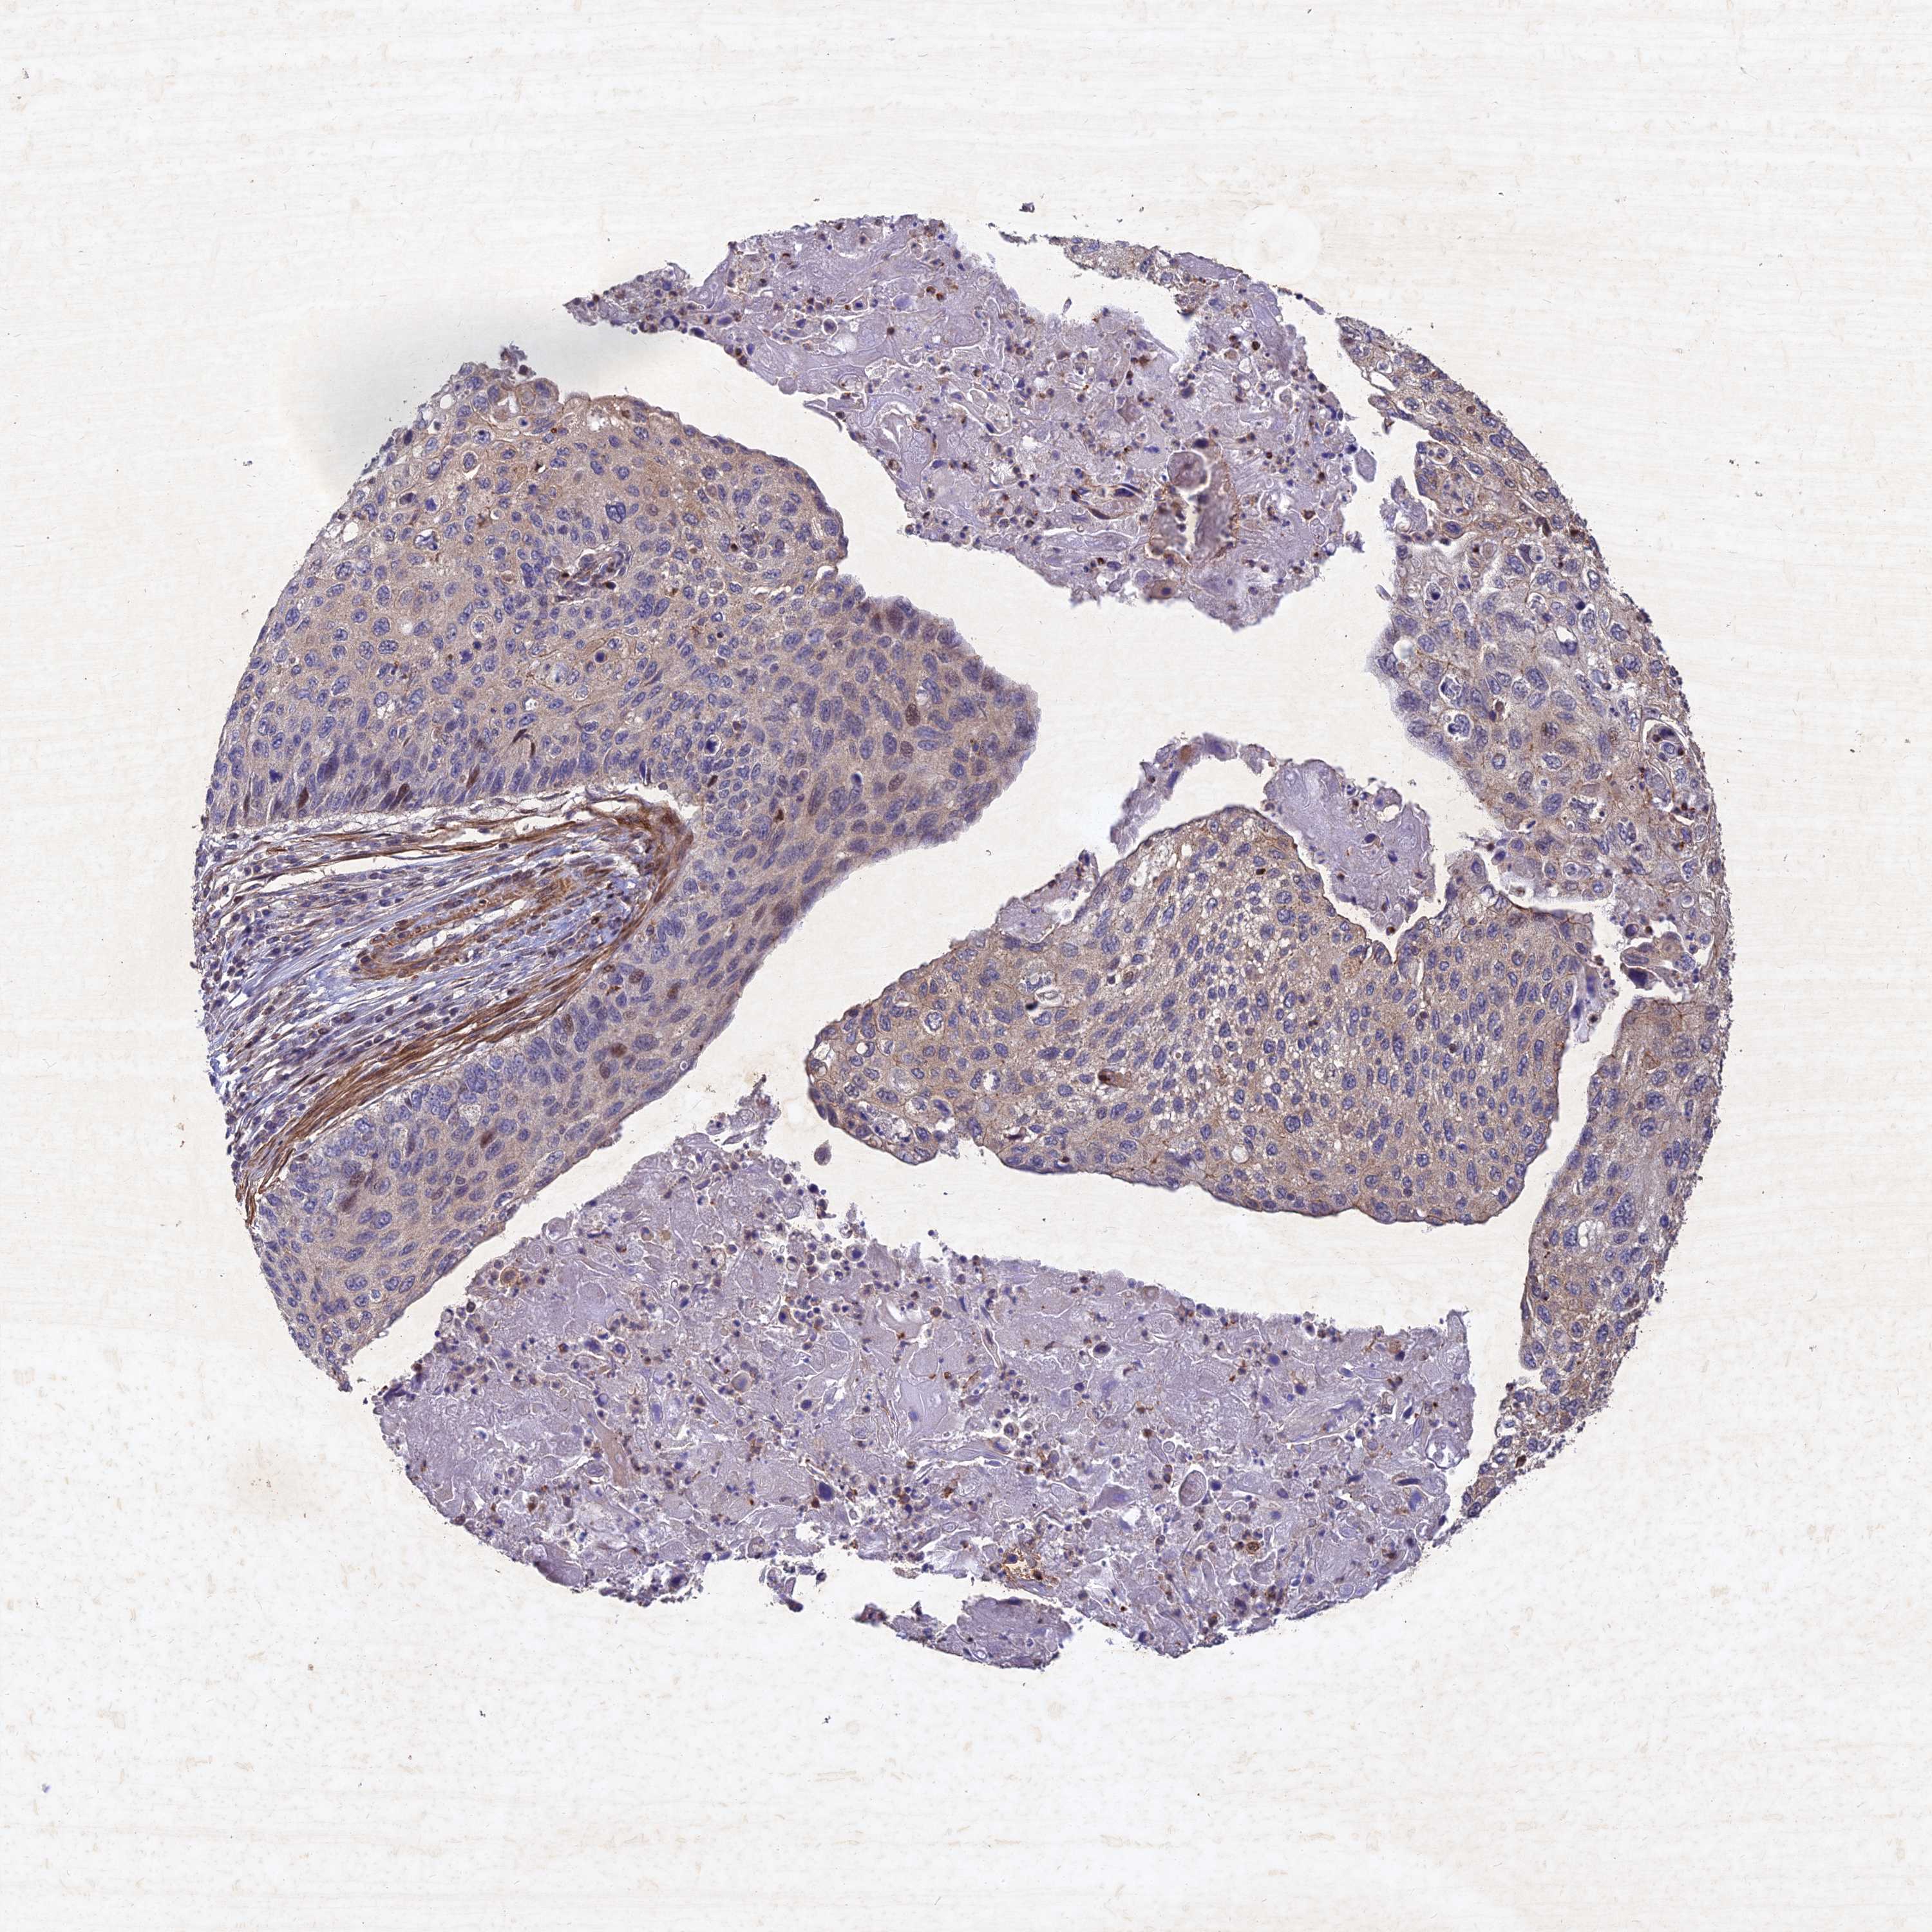

CERVICAL CANCER - Protein expressioni

A mouse-over function shows sample information and annotation data. Click on an image to view it in a full screen mode. Samples can be filtered based on level of antibody staining by selecting one or several of the following categories: high, medium, low and not detected. The assay and annotation is described here.

Note that samples used for immunohistochemistry by the Human Protein Atlas do not correspond to samples in the TCGA dataset.

Antibody stainingi

Antibody staining in the annotated cell types in the current human tissue is reported as not detected, low, medium, or high, based on conventional immunohistochemistry profiling in selected tissues. This score is based on the combination of the staining intensity and fraction of stained cells.

Each image is clickable and will lead to virtual microscopy that enables deeper exploration of all samples and also displays staining intensity scores, fraction scores and subcellular localization as well as patient and tissue information for each sample.

Antibody HPA039708

Antibody HPA040038

Staining

High

Medium

Low

Not detected

Intensity

Strong

Moderate

Weak

Negative

Quantity

>75%

75%-25%

<25%

None

Location

Nuclear

Cytoplasmic/membranous

Cytoplasmic/membranous,nuclear

Squamous cell carcinoma, NOS

Adenocarcinoma, NOS